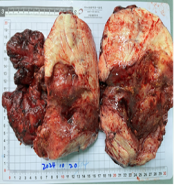

生死抉择:肿瘤侵犯大面积小肠,手术团队果断切除坏死肠段并行小肠造口,保留足够消化吸收功能。

术中病理快检:在肿瘤边缘冰冻切片确认无恶性细胞残留,避免过度切除健康组织。

术后病理确诊为肠系膜纤维瘤,印证了术前判断。